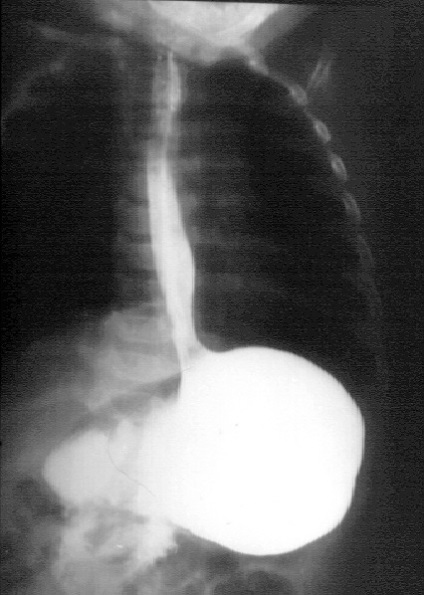

- Examinarea cu raze X a esofagului și a stomacului cu un contrast

Scopul interventiei chirurgicale este de a restabili bariera antireflux, fără a crea obstacole în calea bolului. Nissen fundoplicatură - chirurgie antireflux, în care folie gastric în jurul părții inferioare a esofagului 360 °. creând o manșetă care previne conținutul gastric în esofag. Inainte de operatie, pacientii ar trebui sa fie examinate cu atenție, o atenție deosebită trebuie acordată la ultimul etaj al radiografiei tractului gastro-intestinal pentru a exclude alte posibile boli.